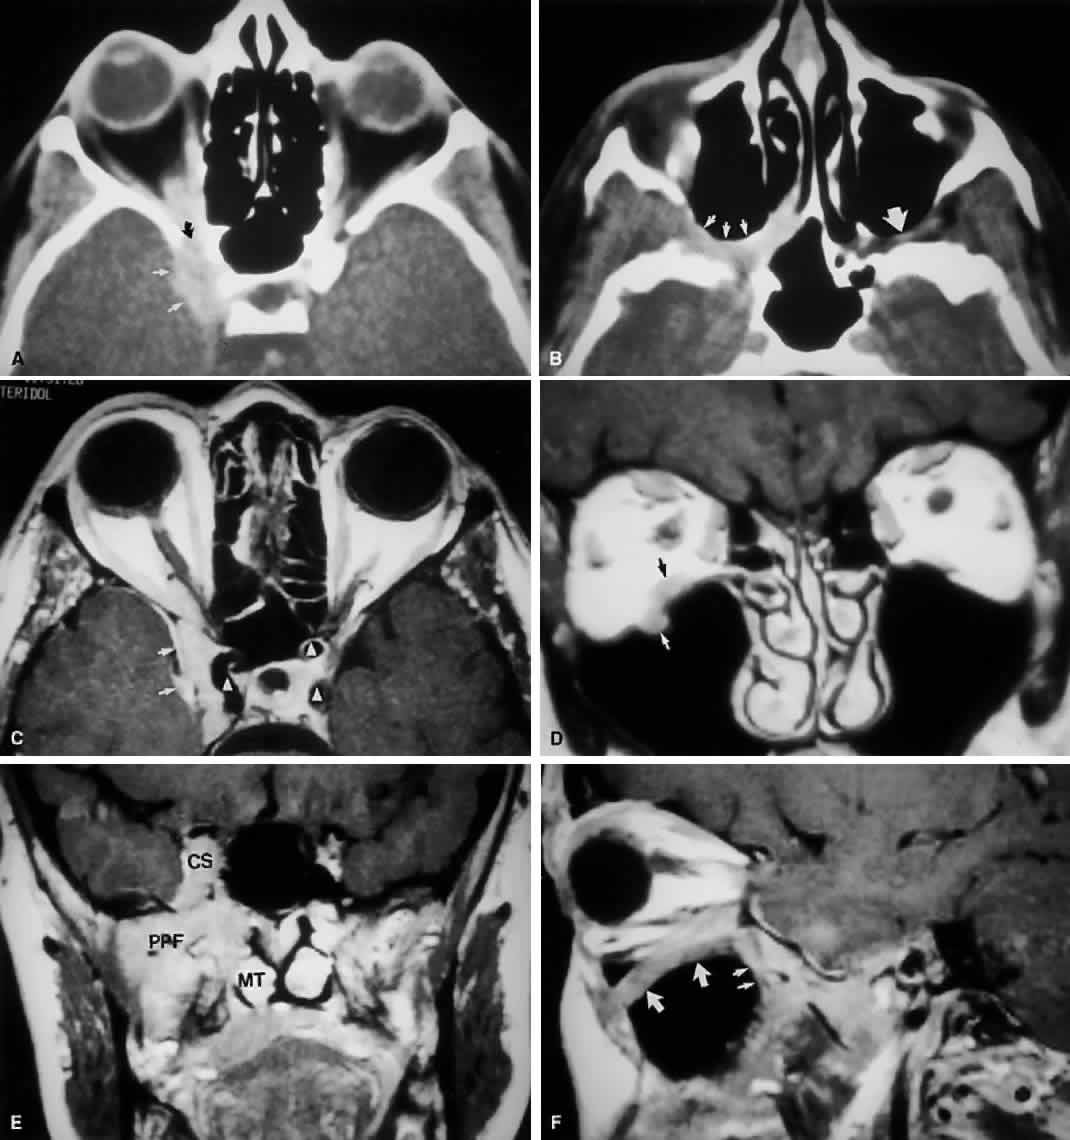

Radiographically, the spaces and foramina of the orbital apex may be considered to lie in three tiers (Fig. 8). The CS is found on the same level as the orbital apex, connecting directly with it via the superior orbital fissure (SOF) to form the middle tier. The inferior tier is formed by the inferior orbital fissure (IOF), which provides direct communication between the orbital apex and the pterygopalatine fossa, a vertically oriented space directly behind the maxillary sinus. Finally, the optic canal has no direct communication with any of the aforementioned spaces and should be considered to lie above the SOF and CS, exiting the orbit in a superomedial course through the body of the sphenoid as the superior tier.26 Orbital apical lesions can therefore gain ready access to the CS and pterygopalatine fossa (Fig. 9). Spread into the cranial vault through the optic canal is usually limited to lesions of the optic nerve (glioma) or nerve sheath (meningioma).

Fig. 8. Coronal CT image (bone window) of the orbital apex in a patient with facial trauma. Note the position of the posterior orbital foramina. The optic canal (A) is always seen in conjunction with the laterally adjacent anterior clinoid process (B) on both axial and coronal views. Slightly lower, the superior orbital fissure (C) communicates with the CS, found directly behind it. The inferior orbital fissure (D) provides communication through the orbital floor with the pterygopalatine fossa.

Fig. 9. An orbital lymphoma involving the skull base provides accentuation of the apical spaces of the orbit. A. On this axial CT, the lesion infiltrates the CS, causing bulging and local invasion of its lateral dural wall (small arrows). Invasion into the orbital apex through the superior orbital fissure (curved arrow) is seen. Note that the patient is slightly rotated in the scanner, because the anterior clinoid and optic canal are visualized on the uninvolved side. B. More inferiorly, the mass has invaded the pterygopalatine fossa (small arrows), located just posterior to the maxillary sinus. On the uninvolved side (large arrow), the fossa has areas of radiolucency, indicating the fat that normally occupies this space. C. Axial MRI, T1-weighted image with gadolinium but without fat suppression. The carotid siphon is seen within each CS as a flow void (arrowheads). Once again, note the inflamed lateral dural wall of the CS and local invasion of the brain parenchyma (small arrows).D. Coronal T1-weighted MR image. The inferior rectus muscle is labeled with a black arrow. The lymphoma has infiltrated the infraorbital canal (white arrow) within the orbital floor. E. Coronal MRI of the orbital apex shows infiltration from the CS to the pterygopalatine fossa (PPF). Because there is no direct communication between these spaces, the lesion must have spread through the superior orbital fissure into the orbital apex, then through the inferior orbital fissure. MT, middle turbinate. The lucency just above the CS is the anterior clinoid process, with the optic nerve within its canal seen as an opacity between the clinoid and the sphenoid sinus. F. Parasagittal MRI shows lymphomatous invasion of the pterygopalatine fossa just behind the posterior wall of the maxillary sinus (small arrows). Note the thickening of the infiltrated infraorbital canal (large arrows) as it travels anteriorly to exit about 1 cm below the inferior orbital rim.